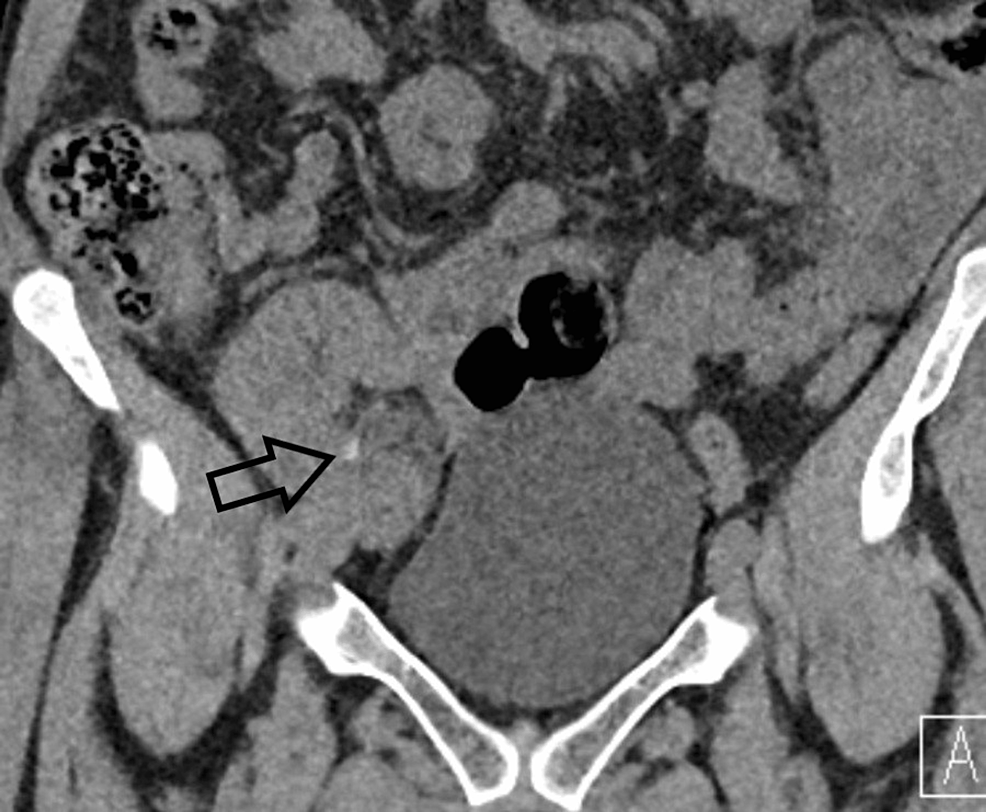

Left ureteric stricture Fig.2. Radiolucent stone Download Scientific Radiolucent Stone In Ct Patients may present with the. Kidney stone disease (nephrolithiasis) is a common problem in primary care practice. Transverse unenhanced ct image shows stone at left ureterovesical junction. Pure uric acid calculi are radiolucent on radiography but can be readily identified on ct. Patients with kidney stones who have a urinary ph of 5.5 or less and whose stones are about. Radiolucent Stone In Ct.

Left ureteric stricture Fig.2. Radiolucent stone Download Scientific Radiolucent Stone In Ct Kidney stone disease (nephrolithiasis) is a common problem in primary care practice. Pure uric acid calculi are radiolucent on radiography but can be readily identified on ct. Patients may present with the. Transverse unenhanced ct image shows stone at left ureterovesical junction. Patients with kidney stones who have a urinary ph of 5.5 or less and whose stones are about. Radiolucent Stone In Ct.